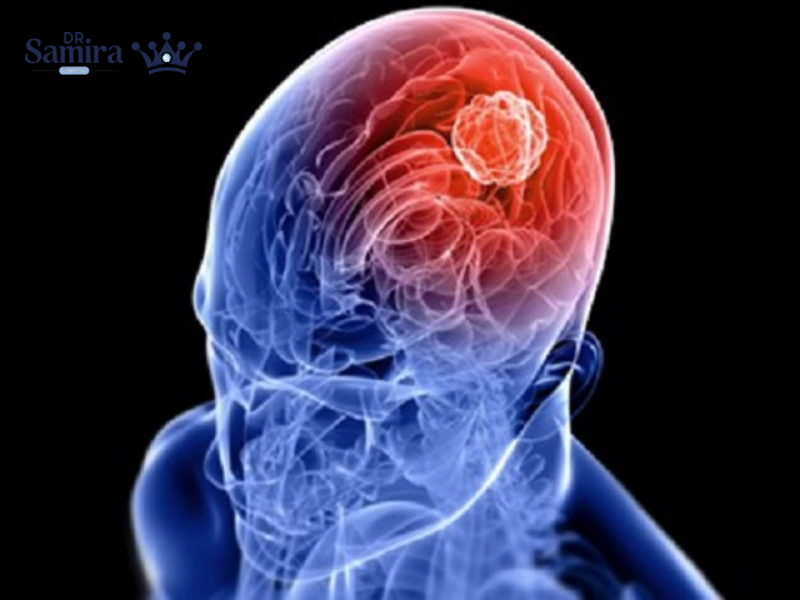

درمان تومور مغزی که یکی از بیماریهای جدی و پیچیده سیستم عصبی مرکزی است، نیازمند تشخیص...

انواع متاستاز به مغز یکی از مهمترین موضوعات در نوروانکولوژی است، چون متاستازهای مغزی شایعترین تومورهای...